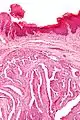

Microscopic histopathological analyses of papillary hidradenoma tumors typically reveal a nodule in the dermis, i.e. layer of skin between the epidermis and subcutaneous tissue. The tumor consists of complex patterns of interconnecting tubular and papillary (i.e. thin finger-like or frond-like) structures.[19] These structures are lined with glandular epithelial and myoepithelial cells. The glandular epithelial cells appear to be excessively proliferating in the ducts leading to the epidermis and show oxyphilic changes, (i.e. cytoplasm filled with large mitochondria, glycogen, and ribosomes) while the myoepithelial cells often appear clear cell-like, i.e. have uncolored cytoplasm when stained with hematoxylin and eosin.[1] The histopathology of anogenital and ectopic papillary hidradenomas are similar to each other.[7][9][15][18]

Very high magnification